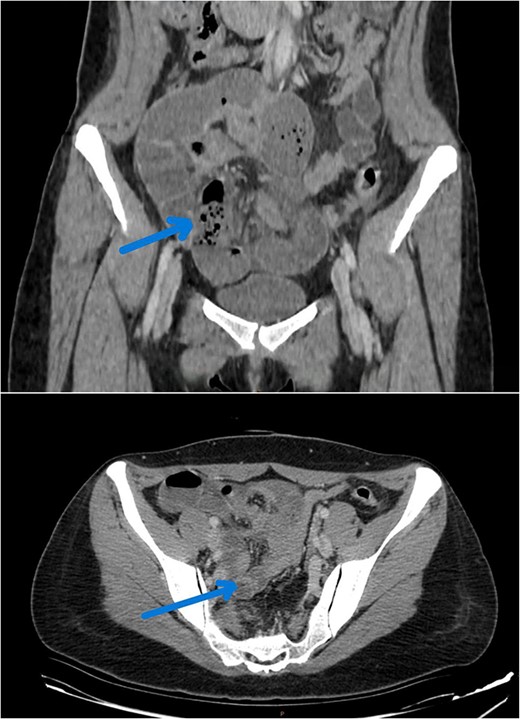

A CT abdomen was conducted due to suspicion of a mechanical small bowel obstruction. The scan revealed a closed-loop dilation of the ileum in the pelvis, near the uterus, caused by an internal hernia through the right broad ligament (Fig. 1). In light of the clinical presentation suggesting small bowel obstruction, an exploratory laparotomy was carried out to evaluate and address the underlying cause.

CT image reveals a closed dialed loop localized to the right of the uterus (arrow).